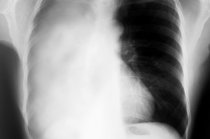

Seguindo à aspiração de um objeto estranho, ocorre acesso de tosse, quadro súbito de chiado no peito8, tosse persistente, falta de ar súbita, rouquidão e lábios e unhas9 arroxeados. Em crianças pequenas, a maior suspeita de que o acidente ocorreu é a situação de engasgo. Se a obstrução for completa e durar mais de três minutos, leva ao coma10 e à morte. Se não chegar a obstruir totalmente as vias respiratórias, mas dificultar a entrada de ar nos pulmões11, a aspiração causará grande ansiedade, agitação e ânsia respiratória. À ausculta12 pulmonar será possível ouvir alguns sons estranhos. Se a obstrução for total, não haverá qualquer som e as extremidades e os lábios estarão arroxeados.

- Se a obstrução for parcial, o melhor procedimento é a não intervenção no ambiente doméstico. Em muitos casos o objeto poderá ser retirado por endoscopia22, mas alguns casos demandam cirurgia.